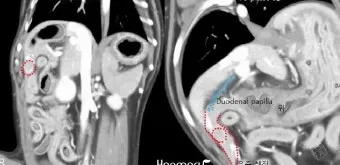

복부 초음파 검사 - 가장 기본적이면서도 중요한 1차 검사예요. 췌장의 크기나 모양 변화, 주변 장기와의 관계를 실시간으로 관찰할 수 있어요. 비용은 보통 15만원-25만원 정도이고, 검사 시간은 20-30분 정도 걸립니다.

CT와 MRI 검사 - 초음파에서 의심스러운 소견이 발견되면 더 정밀한 검사를 진행해요. 특히 3D 영상으로 종양의 정확한 위치와 크기를 파악할 수 있어서 수술 계획을 세우는 데 필수적이에요.